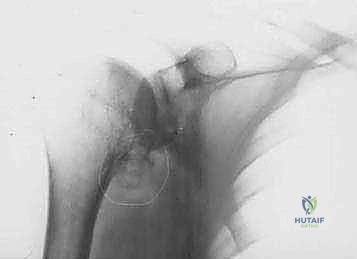

Radiographic findings in primary osteoarthritis include subchondral sclerosis and cyst formation, osteophyte formation, and asymmetrical posterior joint space narrowing ( FIG 4A,B ). 20

A B

A

B C

FIG 4 • Radiographic findings in osteoarthritis include osteophyte formation, especially on the inferior humerus as seen on the AP view ( A ), and asymmetrical posterior glenoid wear with posterior subluxation, as seen on the axillary view ( B ). C. CT scan reveals a large inferior humeral osteophyte and a type C glenoid, with increased glenoid retroversion. D. Coronal MR image in a patient with rheumatoid arthritis reveals an intact but very thin rotator cuff with erosion of the humeral attachment site, and evidence of rotator cuff dysfunction (ie, proximal humeral migration).

D

Computed tomographic (CT) scans are helpful in quantifying bone loss in patients with posterior subluxation ( FIG 4C ).

MRI is useful in patients with rheumatoid arthritis to determine rotator cuff integrity ( FIG 4D ).